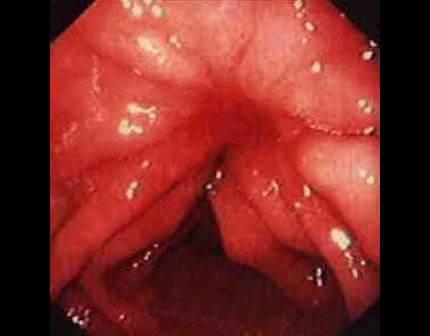

痔瘡癌變的10個前兆

1、痔瘡疼痛加劇:痔瘡患者如感覺疼痛逐漸加劇,可能是癌變的一個信號。

2、痔瘡出血:長期痔瘡出血,尤其是出現持續性出血時,應警惕癌變的可能。

3、痔瘡體積變化:如痔瘡體積在短時間內迅速增大,可能是癌變的征兆。

10、便血顏色變化:如便血顏色由鮮紅色變為暗紅色或混合有黏液,應引起重視。